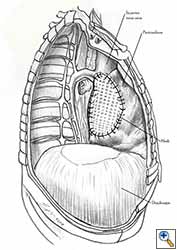

Some pericardial defects resulting after partial pericardiectomy for invasive anterior mediastinal masses need pericardial reconstruction (Figures 4a-c). This is not the case for small pericardial defects, but large and lateral defects require reconstruction, especially if a lung resection has been performed. In the case of pericardiectomy with pneumonectomy, the postpneumonectomy space plays an important role in the pathogenesis of cardiac herniation. En bloc resection of a mediastinal tumor, the pericardium and the lung increases the risk of herniation in a similar fashion. In the absence of a lung resection, lung atelectasis can also increase this risk. Following complex resections requiring vascular resection followed by reconstruction, the reconstruction can stabilise the vascular prosthesis and prevent it from kinking (Figure 4c). Another potential advantage of pericardial reconstruction is that in the event of a re-do sternotomy, the risk of cardiac laceration is reduced because it prevents sternal-cardiac adhesions from forming [5]

Video 1 depicts a pericardial reconstruction with Marlex after a right completion pneumonectomy with pericardiectomy for lung adenocarcinoma (see also Figure 1). The technique of pericardial reconstruction after the resection of invasive mediastinal tumours is illustrated in Figures 8a-c). Video 2 depicts a pericardial reconstruction with Mersilene mesh after the resection of a malignant thymoma invading the anterior pericardium (see also Figure 4b). The technique of right pericardial reconstruction after extrapleural pneumonectomy is illustrated in Figures 9a and 9b). Video 3 depicts a pericardial reconstruction using Gore-Tex Dual Mesh after a left extrapleural pneumonectomy (see also Figure 3). Care must be taken to prevent constriction (Figure 10).